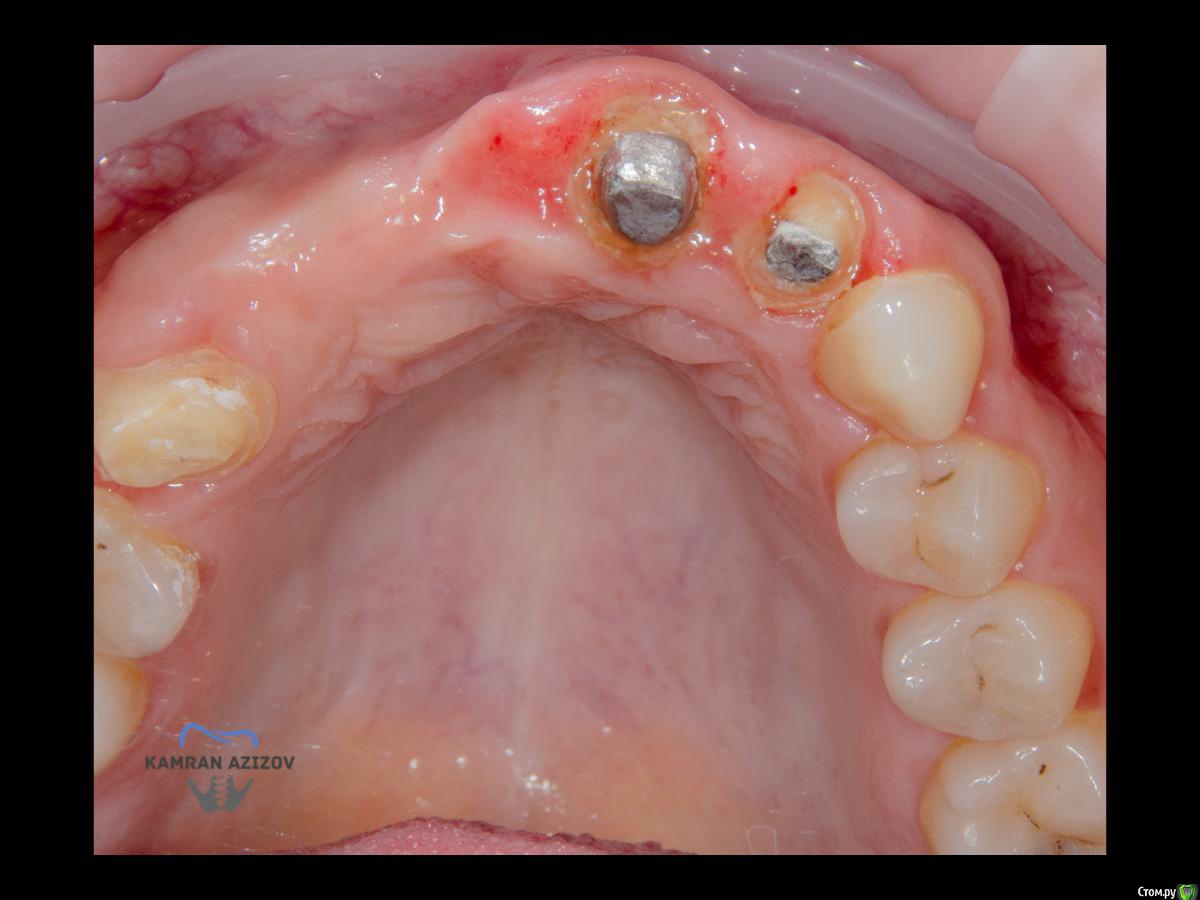

kamranchick Опубликовано 6 апреля, 2019 Поделиться Опубликовано 6 апреля, 2019 (изменено) Хай Гайсдавно ничего не комментировал и не выкладывал, что то настроения не было, да и муза не посещалаСитуация следующаяпришла пациентка, жалобы на неприятный запах из рта, сначала не понял что за хрень, ну как распилил мост понял че к чему... халтура.Ну и по кейсуУдаление клыка и 2ки, через 2 месяца навигация, имплантация + Шашлыки по карлоссу, смена формиков, временное протезирование. только мягкие ткани, Изменено 6 апреля, 2019 пользователем kamranchick 7 1 Ссылка на комментарий